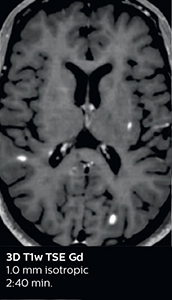

This is an example of acute ischemic stroke with distal occlusion of the right posterior cerebral artery. Note the improved visibility of the ischemic territory on the diffusion weighted image with high b-value. The 3D FLAIR shows a distal PCA occlusion. The fast SWIp depicts the thrombus on the isolated second echo image. The total scan time (including SmartBrain, preparations and a fast 3D T1w TSE Gd) is 8:00 minutes.

Dr. Savatovsky appreciates the improvements and flexibility that Elition with Compressed SENSE and MultiBand SENSE provides, particularly for stroke patients. “For stroke, it allows us to cut about 5 minutes off of our stroke protocol, or to keep the same acquisition time and get more insights.” The ability to perform more sequences can help in making a swift and confident diagnosis. “For example, our stroke cases usually include the regular sequences that every center does (b1000 diffusion, FLAIR, time-of-flight angiography), but we also image supra aortic vessels, and we can replace a gradient echo sequence with a fast 50-second susceptibility-weighted sequence, and all of this doesn’t add much time. because all the regular sequences are accelerated on Elition.” “The time savings with Compressed SENSE and MultiBand SENSE make it easier to add sequences to give us additional insights. Depending on the context and the first results, we might add a DSC perfusion to assess the ischemic penumbra, an ASL perfusion to help find an alternative cause in case of normal diffusion, or add a high-resolution T1 sequence for a stroke patient, to quickly assess wall imaging in emergency cases. The additional sequences can help improve patient management, because we can already consider some alternative diagnoses if the morphological MRI is normal.”